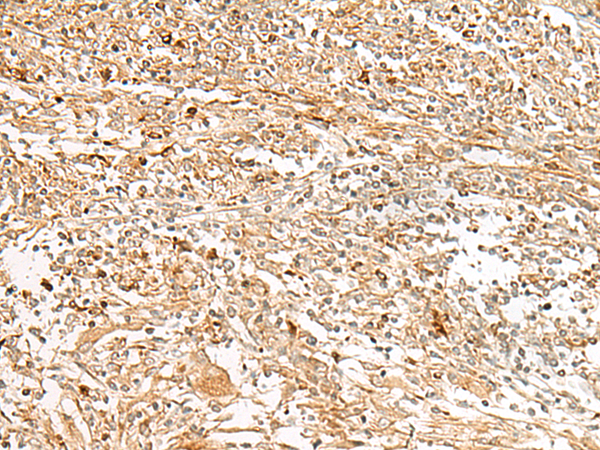

分类: 科研抗体货号: P43586别名: GPCR; PGR7; GALR4; GALRL; GPCR-2037应用: IHC反应种属: Human

分类: 科研抗体货号: P43585别名: ZAQ; PKR1; GPR73; PK-R1; GPR73a应用: IHC反应种属: Human

分类: 科研抗体货号: P43567别名: CP7B; CBAS3; SPG5A应用: IHC,IF反应种属: Human

分类: 科研抗体货号: P43566别名: PCTK3; PCTAIRE; PCTAIRE3应用: IHC,IF反应种属: Human